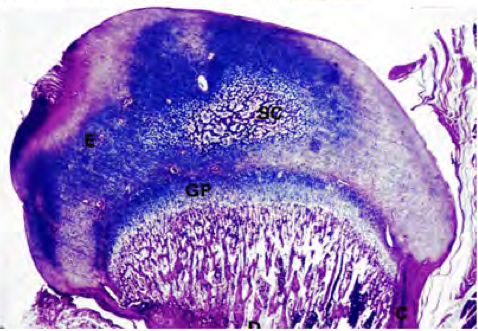

Secondary ossification center; H&E

Bones grow longways (interstitial growth) at secondary ossification centers like the one shown on this slide. And, despite what your mothers might have you believe (memories of me crying with milk dripping down my chin as my mother stands over me with a wooden spoon and a tape measure come to mind)-- bones grow quite slowly and even gallons of milk will have no immediate results. In fact, if it was a race, this nice little snail I drew would win every time.